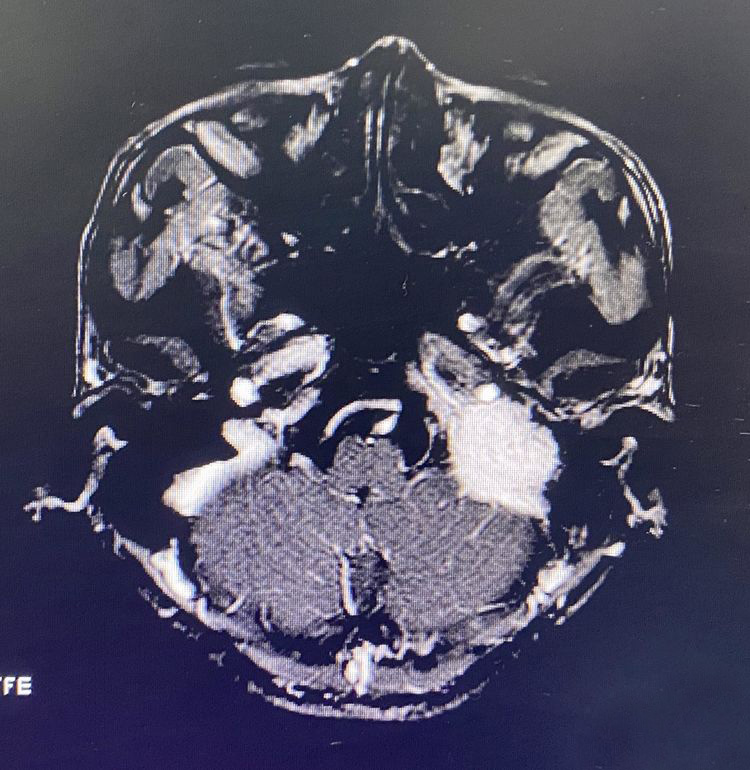

延肿瘤边界整块分离切除肿瘤,在颈静脉孔内有多个出血的静脉孔道用明胶填塞止血。全切肿瘤后暴露完整瘤腔。

中等大小的球瘤在完整暴露边界的前提下控制出血是可期的,过去我并不会完整暴露面神经垂直段在其下方的部分切除时由于是盲掏,常常带来大量出血,因此这次改变战略,使用经典的方法,看来经典之所以经典是有道理的。不过暴露肿瘤边界的过程所需时间却是切除肿瘤的2-3倍😭。暴露后明显感觉手发麻,背发酸,做颅底是真苦!